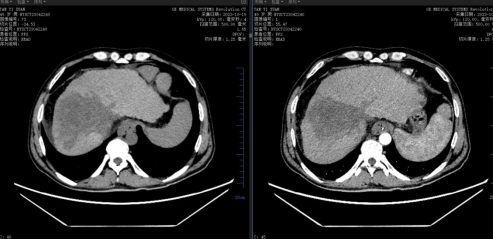

省肿瘤医院CT图像:

2023.10.19复查肝脏CT提示:肝脏左右叶比例失调,肝裂增宽,肝S4段见巨大实性不规则团块状低密度影,最大截面约9.3*7.2cm,增强后无明显强化,其周围并伴相似性质结节影,肝动脉左侧枝及门静脉左侧枝受压,右动脉S8段分支、门静脉右前段分支及肝中静脉显示不明显,脾大,密度均匀,未见异常强化,脾脏周围及食管静脉曲张